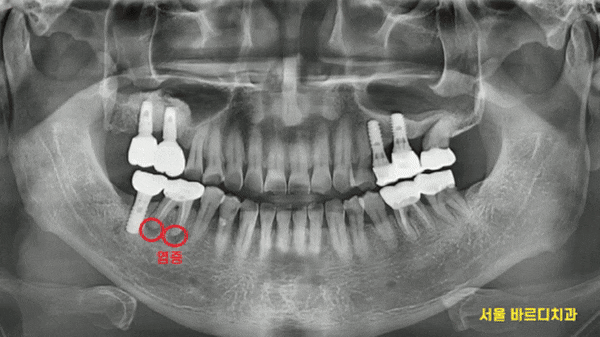

x-ray를 보실까요~?

24.03.29

오른쪽 아래 치아 뿌리 끝에 염증이 있습니다.

원인 해결이 안되니

반복적으로 잇몸 풍선마냥

부풀었다 가라앉았나보네요